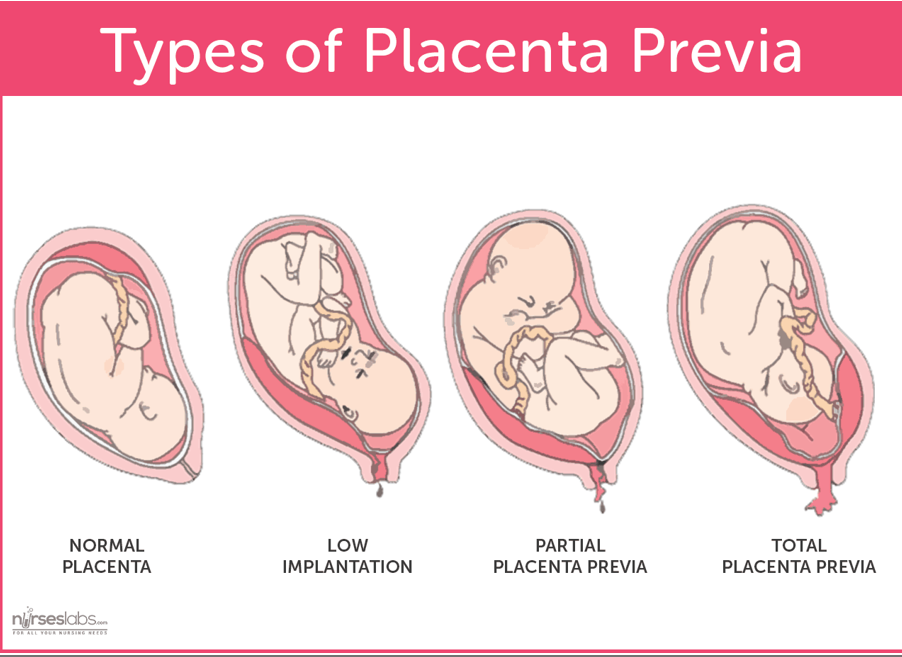

Placenta praevia

Le placenta praevia correspond à une anomalie de localisation du placenta, inséré trop bas dans l’utérus, c’est-à-dire sur son segment inférieur (partie inférieure) , pendant la grossesse.

On distingue classiquement 3 variétés de placentas praevia :

- Le placenta praevia central ou placenta recouvrant total. Il est à l’origine d’une obstruction complète de l’orifice interne du col utérus. Dans ce cas, l’accouchement par voie naturelle est impossible et nécessite une césarienne.

- Le placenta praevia marginal ou recouvrant partiel. Il affleure l’orifice interne du col de l’utérus.

- Le placenta praevia latéral. Il s’insère sur le segment inférieur, à distance de l’orifice interne du col de l’utérus.